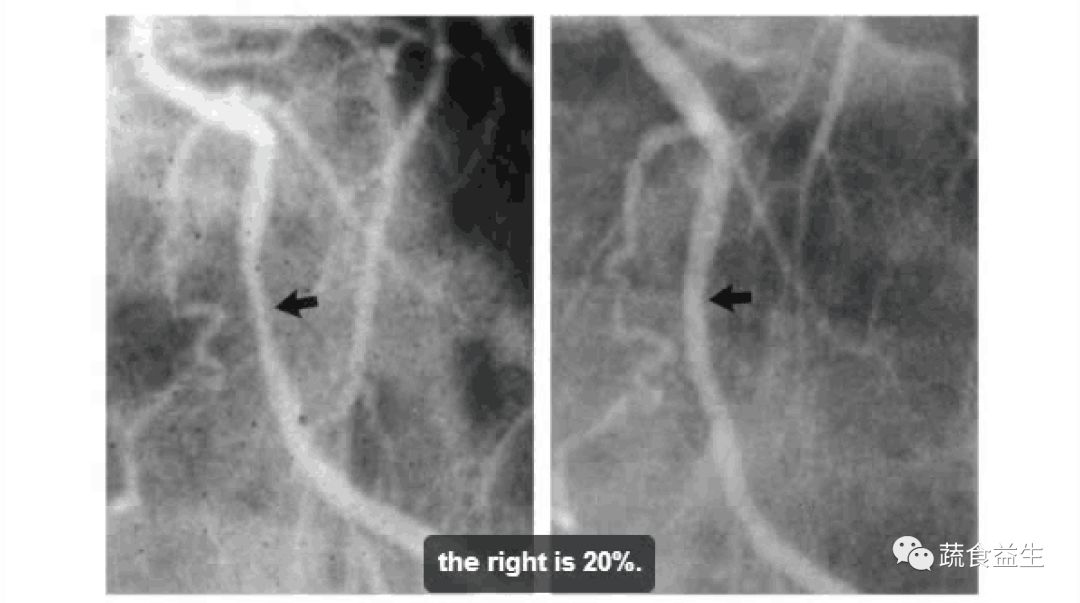

以下是几个人的心脏血管造影图:

1. 67岁儿科医生,血管堵塞改善10%。

2. 58岁工厂工人,血管堵塞改善20%。

两年半后,他又做了一次心脏造影检查,这次的检查结果是这样的:

堵塞的心血管已经疏通,心脏病已经逆转啦!